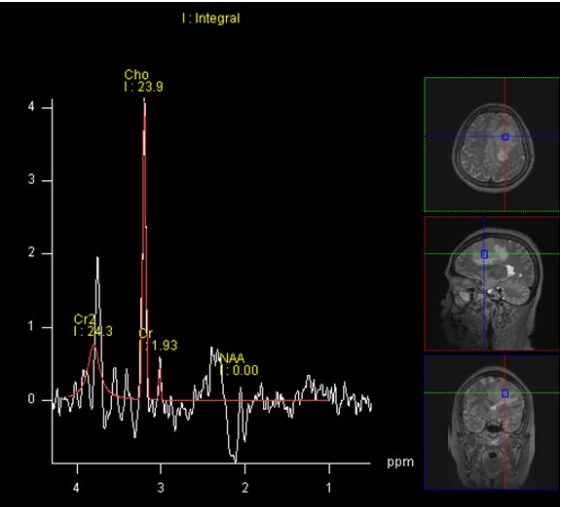

MRS:起源于脑外,Cho 均显著增高,NAA 峰一般不显示或因瘤周脑组织干扰呈低峰显示